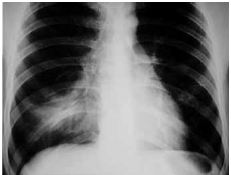

Mulher de 46 anos de idade, previamente hígida, há 3 dias queixava-se de tosse, febre, dispnéia e expectoração amarelada, resolvendo procurar o pronto-socorro. Ela negou etilismo ou tabagismo. Ao exame físico: corada, hidratada e febril (38,1 ºC); PA: 110 x 70 mmHg, FC: 96 bpm, saturação de oxigênio: 94% e frequência respiratória: 20 ipm; ausculta pulmonar: crepitações no terço médio de hemitórax direito. Cardíaco e abdome: normais. Radiografia de tórax: mostrada a seguir.

Em relação à conduta inicial, assinale a alternativa correta.